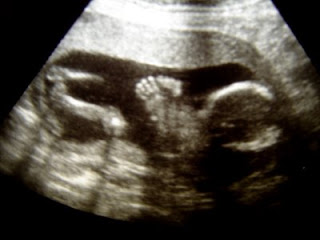

So I found out if I am having a niece or a nephew and it is.......

What do you think? BOY? GIRL?

Aaron and Jaime went to have another ultrasound done on Friday and this time they were able to see clearly that the baby is a ..........................

I'm so excited for the girls to have a girl cousin to get to play with on top of Garrett. Madeline and Garrett already have the best time together. Aaron and Jaime are excited to be having a beautiful little girl. Her name will be Lyric London Caldwell. ( I hope that is right. Correct me if I'm wrong, Jaime). Of course, I have TONS of clothes for her already. We can't wait for her to get here (late January). At least now we can quit calling her IT. I know she will have her daddy so tightly wrapped around her finger he won't know what happened. Jaime will have her shopping buddy and Aaron has his sports buddy. Congratulations guys!! We love you. Let me introduce you to my niece............

Profile Picture.

Showing "girl parts"

Pretty cute huh?